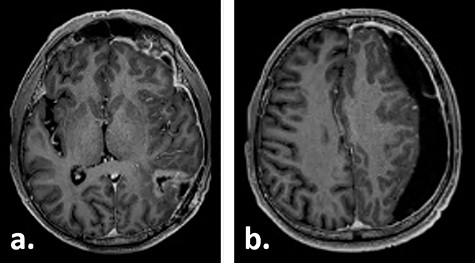

Fifteen weeks after tumour resection and 4 weeks after hygroma evacuation, the patient presented again with concentration loss, fatigue and a moderate right-sided hemiparesis. A new CT scan revealed a strongly progressive subdural hygroma with a 3-mm-thick subdural membrane. The hygroma was evacuated through the same burr hole; however, due to an unsatisfying hygroma regression, a subduro–peritoneal shunt for permanent hygroma drainage was implanted subsequently. During these both procedures, a thick greyish subdural membrane was noticed, but no tissue samples were taken. Despite the volume reduction of the hygroma, its membrane still caused a considerable mass effect. Few days after the last surgical procedure, a cerebral MRI was performed following the tumour follow-up protocol. On this imaging, the subdural membrane over the left hemisphere presented as an inhomogeneous contrast-enhancing lesion with irregular contours (Fig. 3).

Gadolinium-enhanced T1-weighted axial MRI of the patient 16 weeks after tumour resection demonstrating the resection cavity (a) and progressive subdural fluid collection with the newly occurred contrast-enhancing membrane (b).